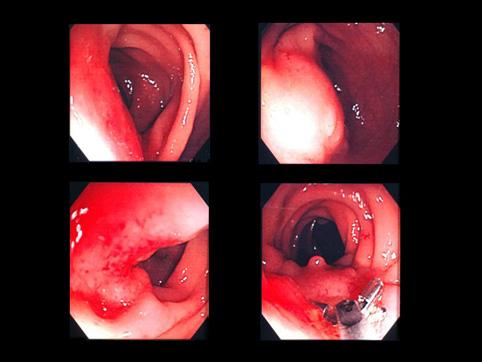

A case of endometriosis of the upper part of the rectum that required a partial resection.

[ Image ID:10735 ]

Tumor-like lesions/Endometriosis

Large intestine(Colon)/Rectum

Endoscopy

40 -